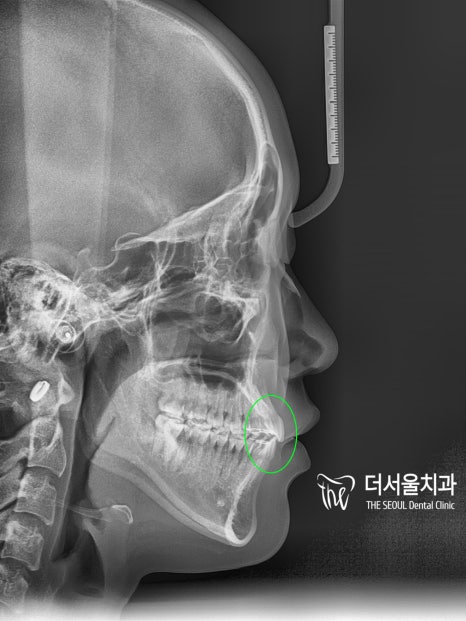

측면 ceph을 비교해 보면

입술의 긴장감이 사라져

자연스러운 모습으로 바뀌었습니다.